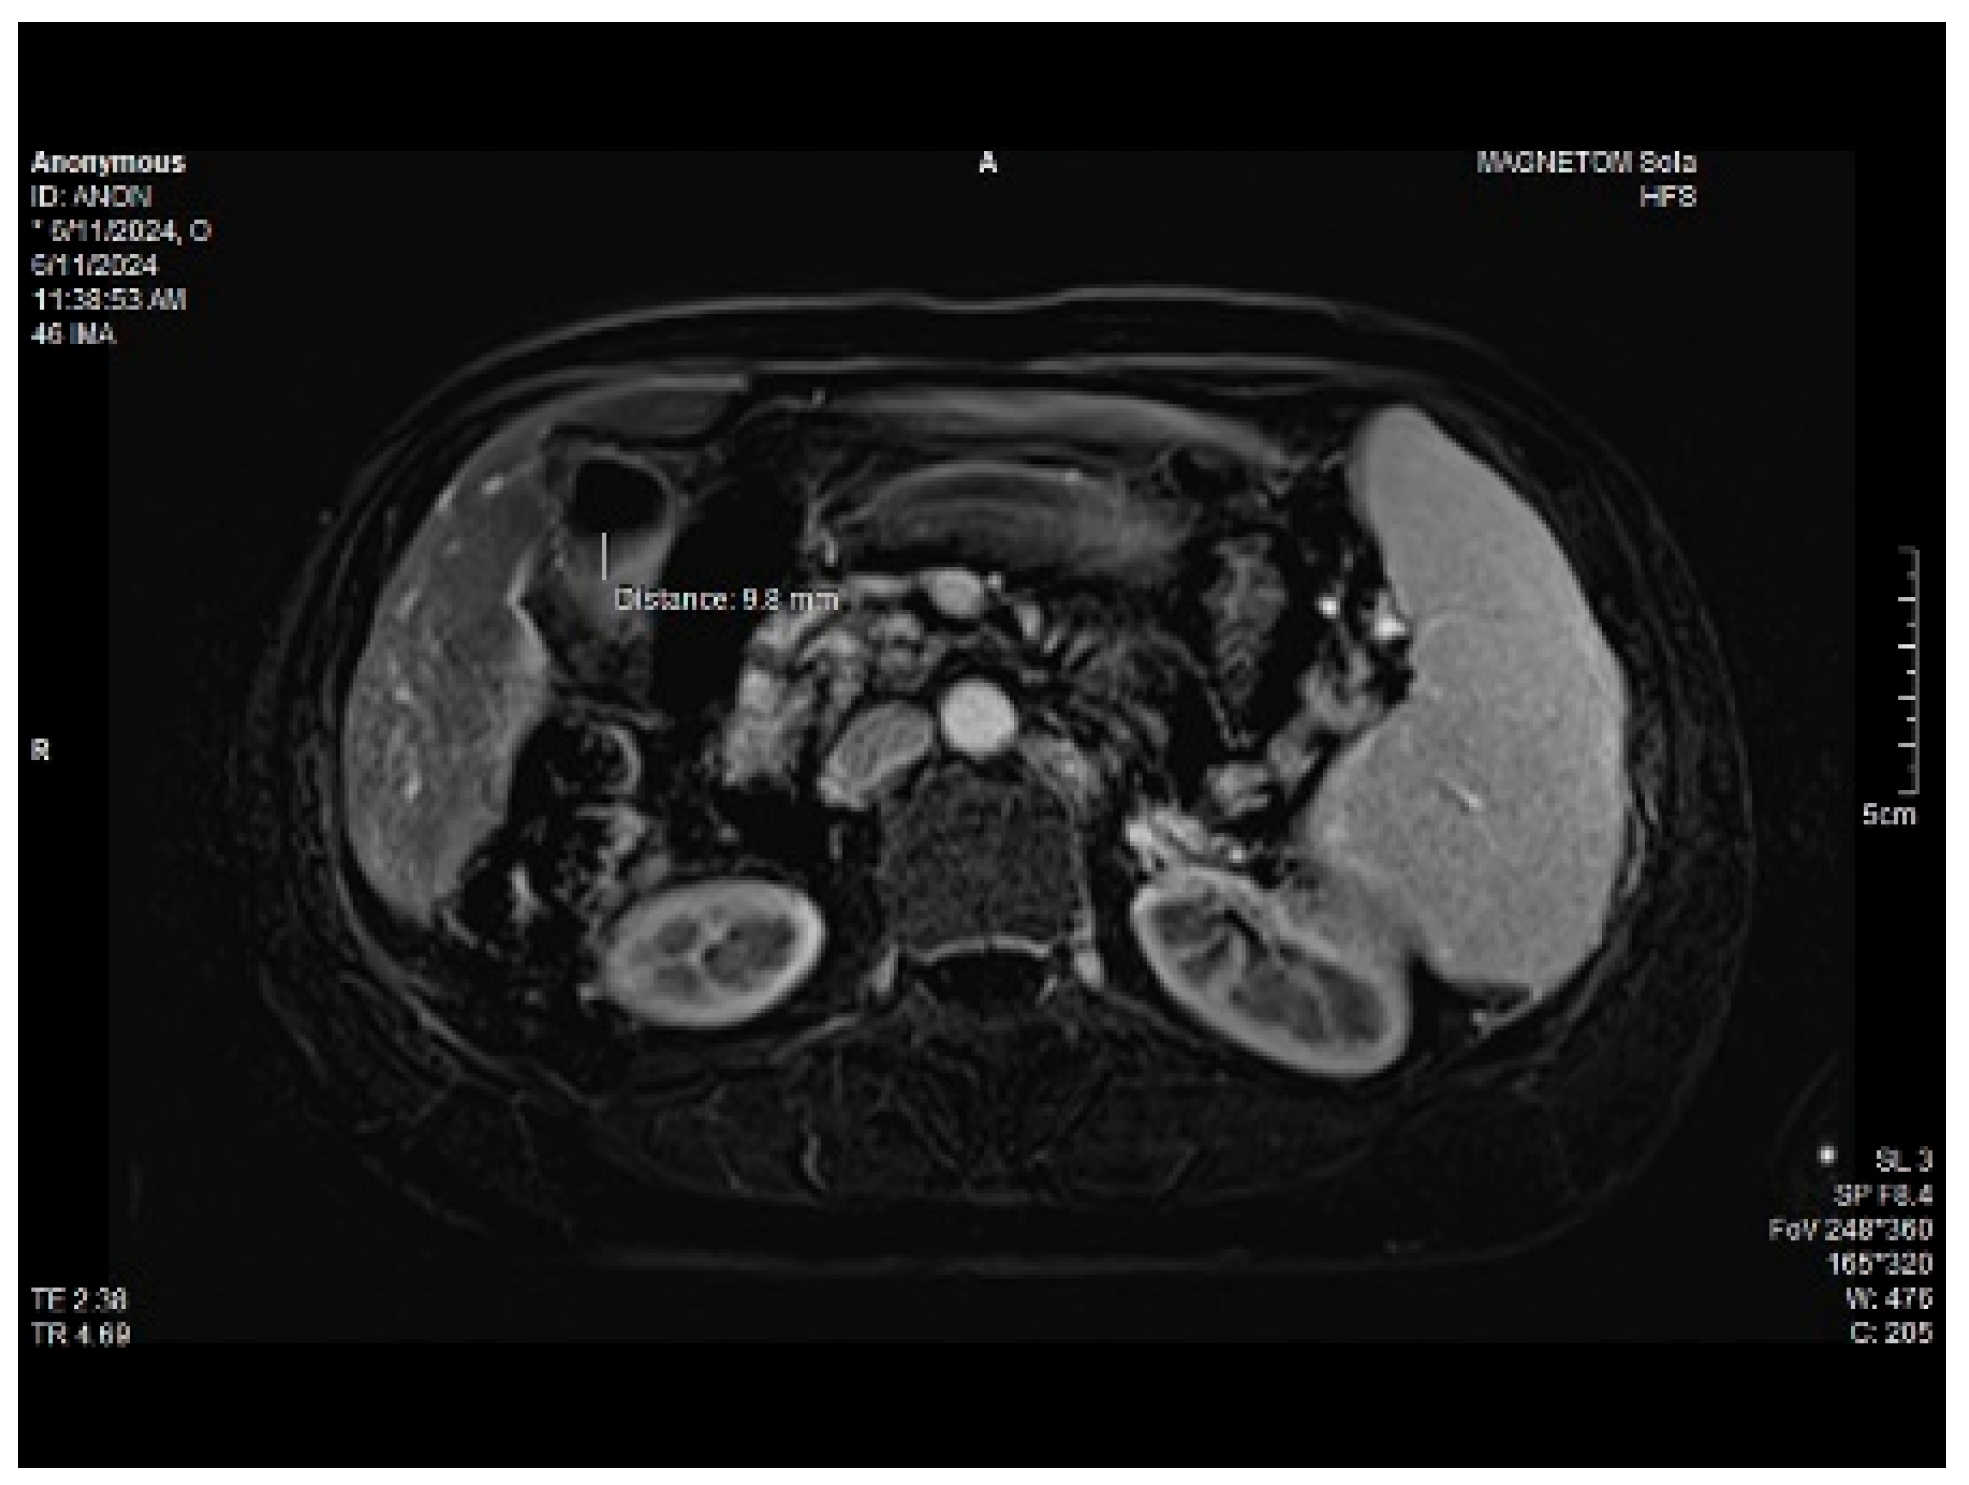

Abdominal MRI study confirmed the hepato-splenomegaly, ascites and the patency of the portal vein system. In addition, small veno-portal shunts were highlighted at the periphery of both hepatic lobes. Various MRI features are depicted in Figure 6, Figure 7, Figure 8 and Figure 9.

Figure 9. Small veno-portal shunts visible at the periphery of both hepatic lobes: MRI aspects.